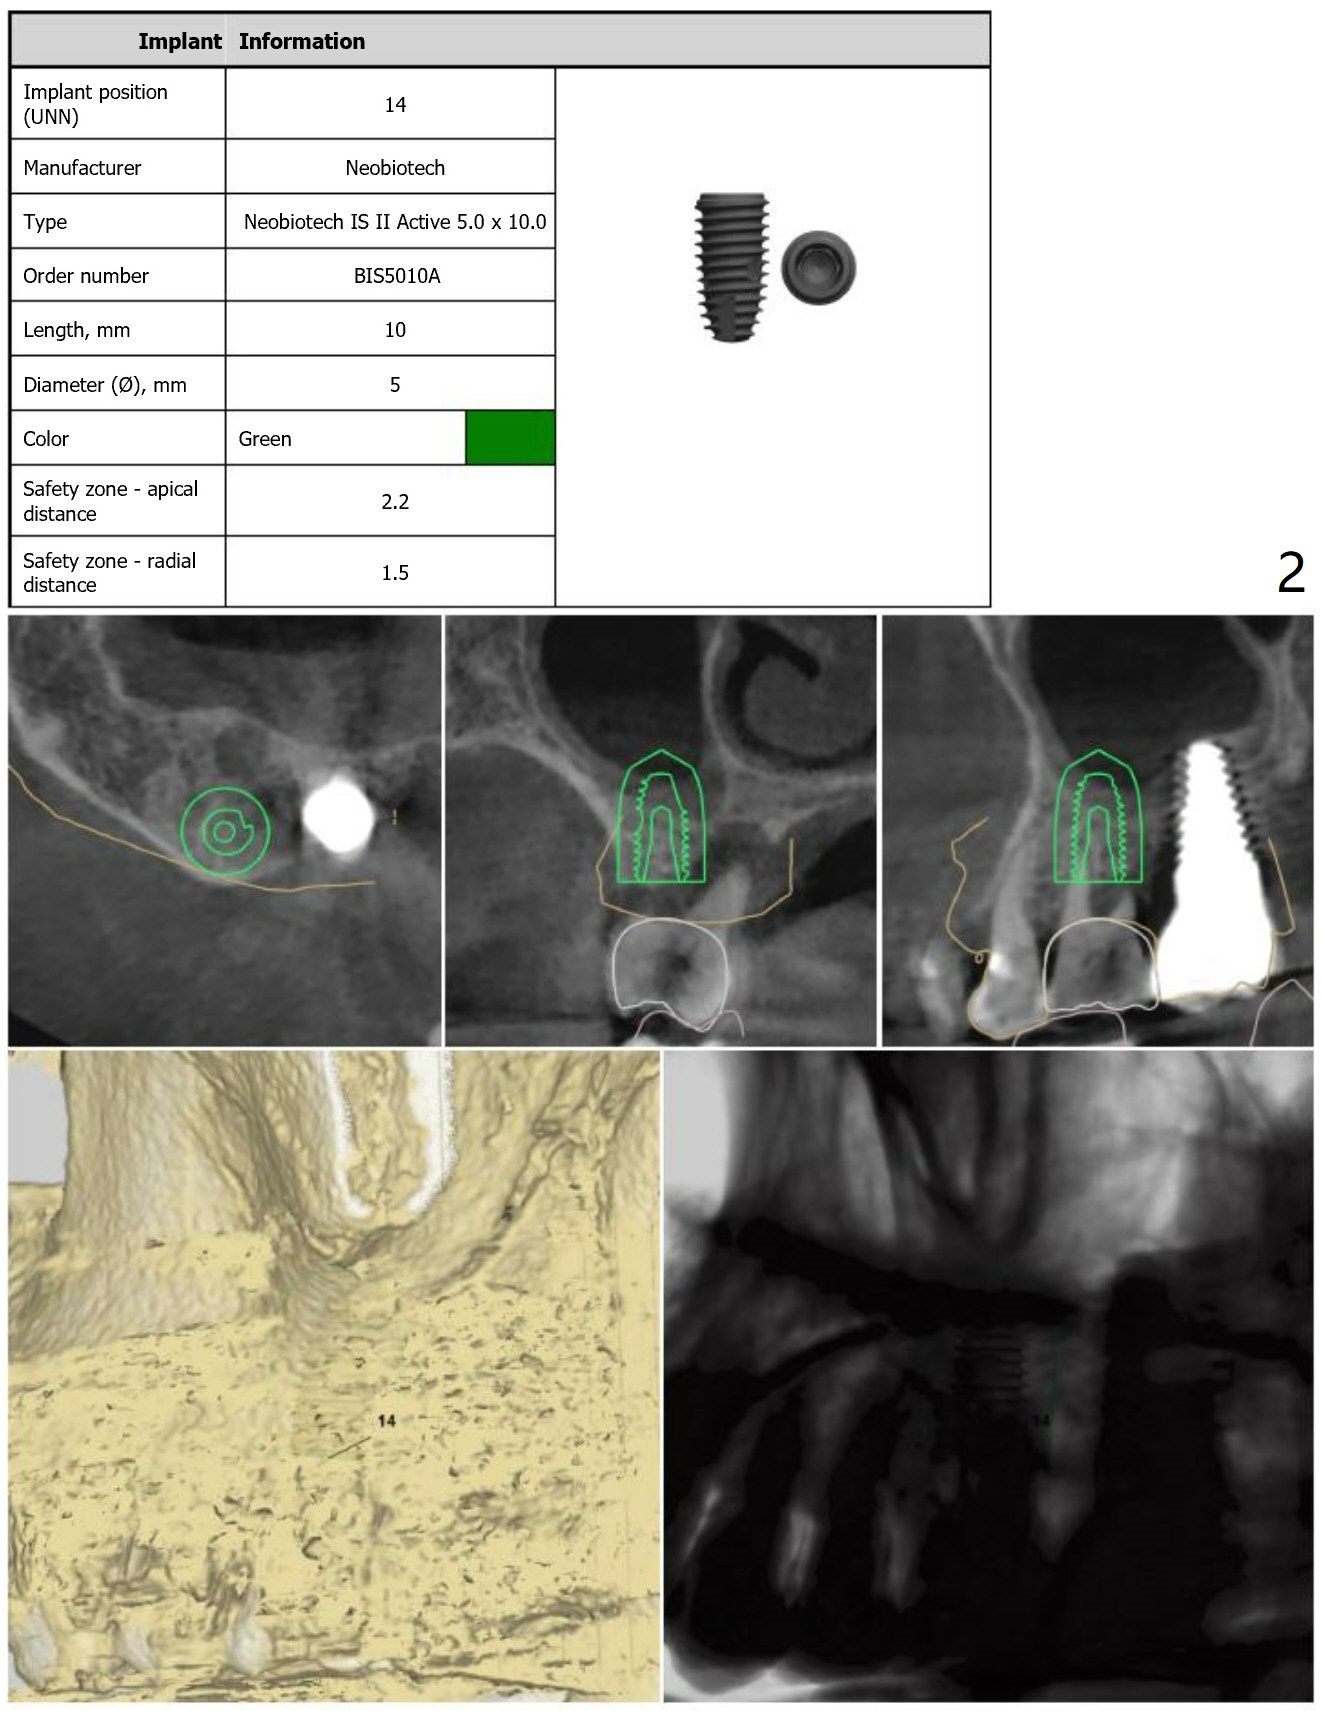

A 61-year-old woman, 2-3 PRF membranes for sinus lift and palatal wall defect repair. In fact a 5x14 mm Tatum implant will be placed to prevent screw loosening.